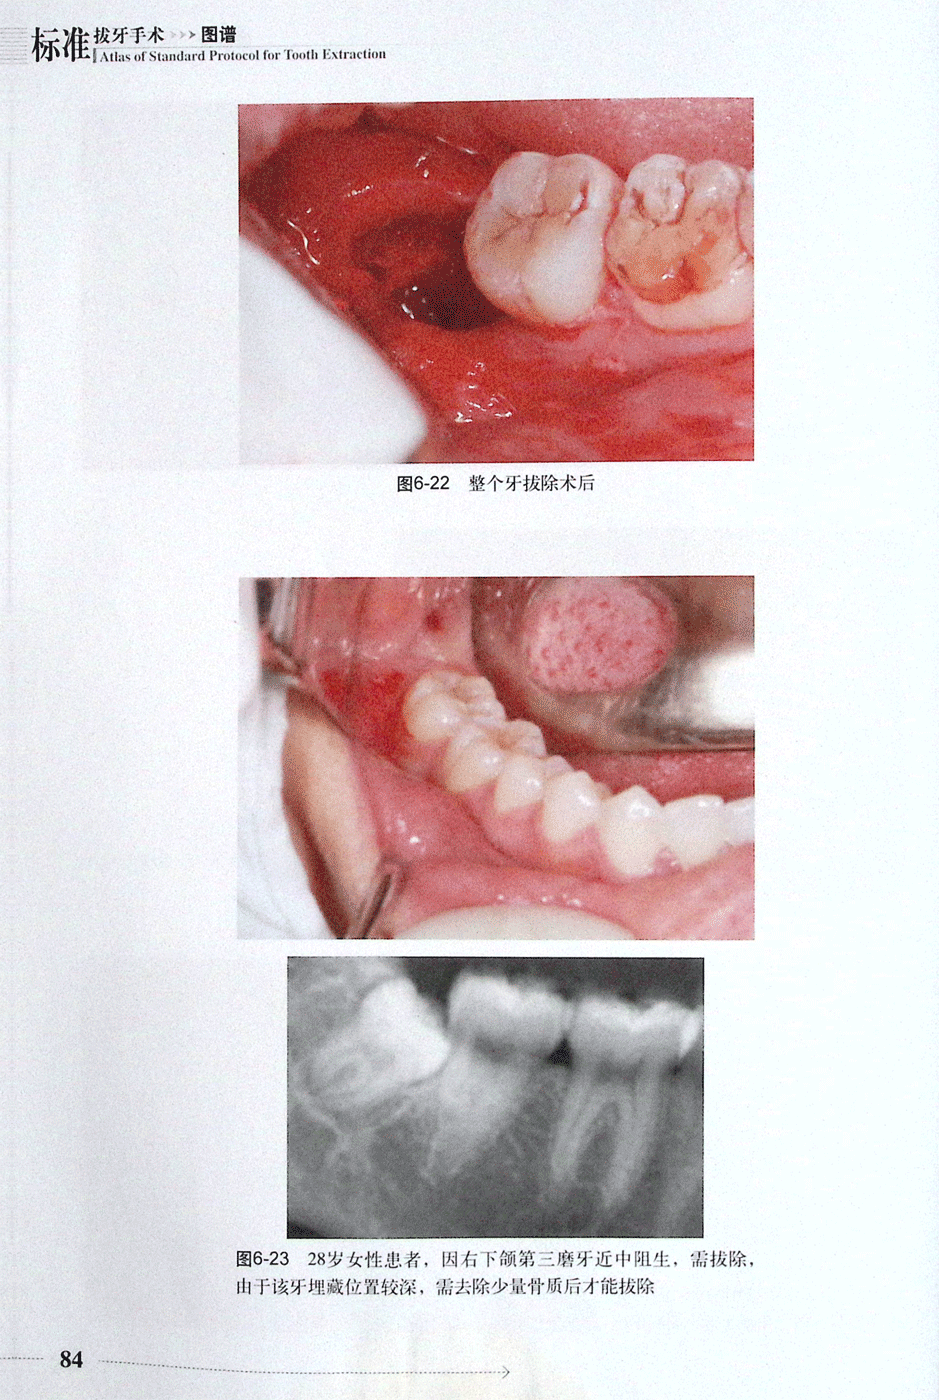

不同类型阻生牙的拔除:近中阻生(二)